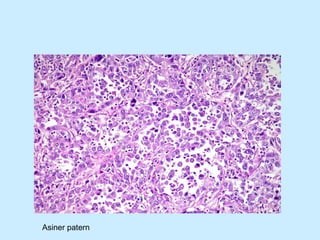

Adenokarsinomda asiner patern

Asiner patern oluşturmuş, veziküle nüveli, nükleol belirginliği olan, eozinofilik, yer yer berrak sitoplazmalı adenokarsinom hücreleri

Asiner patern